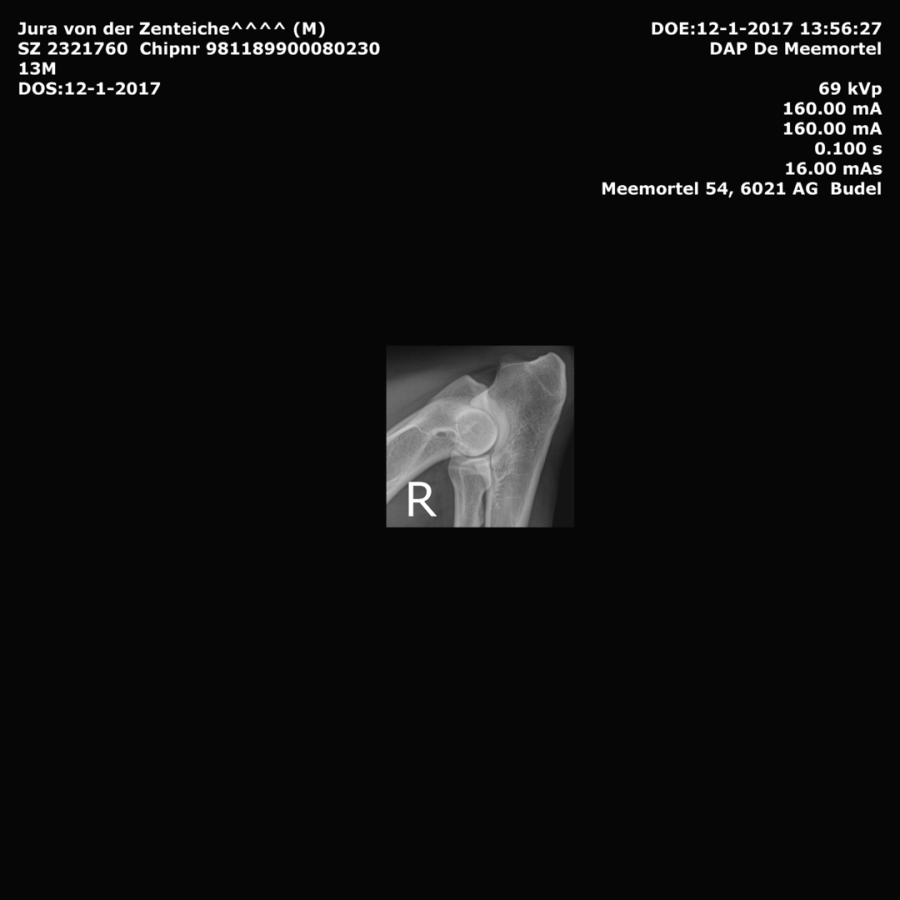

Jura's Right Elbow Xray